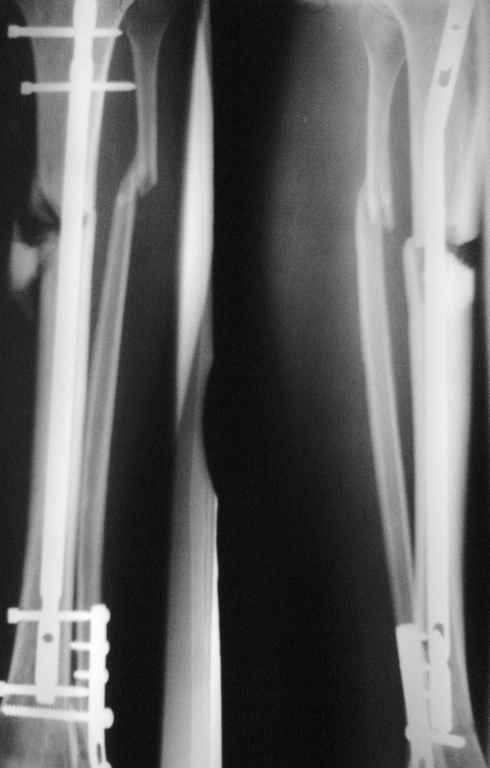

Б-й О.25лет прооперирован 7 мес. назад, сформировался пролежень ок. 2-х мес назад.Передвигается с 50% нагрузкой с помощью трости.

Предлагается остеотомия м/берцовой кости,удаление фрагмента, динамизация стержня с введением поллерного винта.

Какие варианты в данной ситуации возможны?